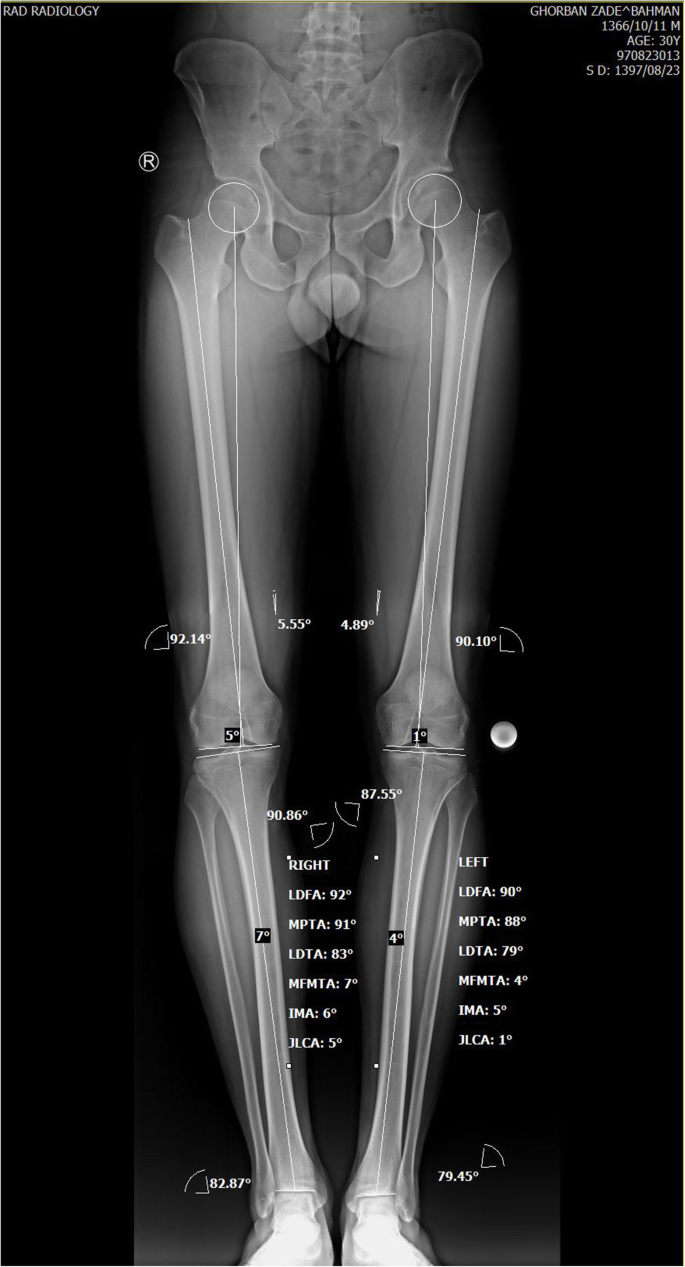

Based on the patient’s standing triple joints alignment view, our patient’s varus angle was 7o and according to his Medial Proximal Tibial Angle (MPTA) (90.83o) and Lateral Distal Femoral Angle (LDFA) (92.21o), the varus deformity was assumed to be of femoral origin (Fig. 1). So, it was decided to perform distal femoral valgus osteotomy to correct varus malalignment. No significant femoral/ tibial length discrepancy existed comparing both sides (femoral and tibial length of 492 and 413 mm on the right side consecutively; femoral and tibial length of 493 and 417 mm consecutively on the left side). Instead of lateral closing wedge osteotomy, it was preferred to perform medial side opening wedge valgus osteotomy as the former might interfere with femoral tunnel drilling during ACL-R. Using the mediCAD ® software, it was analyzed that at the osteotomy opening, the angle between proximal and distal fragments should be increased to 7 degrees and the space between the proximal and distal fragments should be increased to 10 mm at the medial cortex.

Despite describing and evaluating simultaneous HTO and ACL-R by many studies, [4, 12,13,14,15], only a few have described simultaneous ACL-R and DFO [2]. In our case, as the deformity had femoral origin (MPTA = 90, LDFA = 92), the valgus osteotomy was carried out in the distal femur.